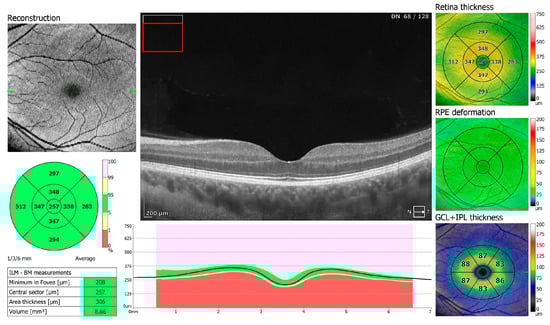

Figure 2.

OCT 3D macula scan 7 × 7 mm of COVID-19-negative patient. RPE, retinal pigment epithelium; GCL + IPL, ganglion cells layer + inner plexiform layer; ILM–BM, inner limiting membrane–Bruch’s membrane.